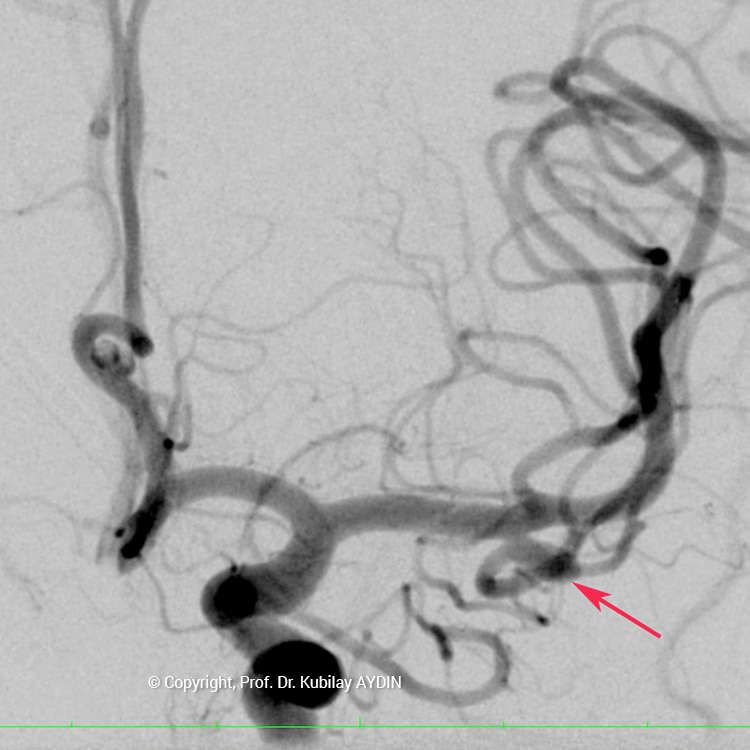

Tüm kapalı anevrizma tedavileri, hasta genel anestezi ile uyutularak gerçekleştirilir. Kapalı anevrizma tedavisinin tüm aşamaları, bacak atardamarı içine yerleştirilen 2 mm çaplı (kurşun kalemden daha ince) bir özel kateter yoluyla uygulanır. Bu küçük giriş noktasından damar içine çok ince (0.5mm çapında) ve yumuşak yapıda mikrokateter adını verdiğimiz özel plastik tüp gönderilir. Anevrizmayı kapatmak için kullandığımız bu mikrokateter, anjiografi cihazında izlenerek anevrizmanın bulunduğu damar içine yönlendirilir. İçi boş, çok ince ve yumuşak bir plastik tüp şeklinde olan mikrokateterin ucu, anevrizma kesesi içine yerleştirilir. Daha sonra bu mikrokateter içerisinden gönderilen platinden yapılmış çok yumuşak “koil” adı verilen tellerle anevrizma kesesi doldurulur. Koiller, anevrizma kesesi içinde bir yumak oluşturup, anevrizma içine kan girişini engeller. Anevrizma kesesi, koillerle tamamen doldurulup, anevrizma içine kan girişi tam olarak durduğu zaman, mikrokateter anevrizma içinden geri alınarak işlem tamamlanır. Anevrizmanın koil adı verilen özel tellerle doldurularak kapatılma işlemine, "koilleme" adı verilir. Anevrizmanın koillenerek kapatılması işlemi, oldukça güvenli ve etkili bir tedavi yöntemidir. Kanamamış beyin anevrizması olan hasta, koilleme yöntemi ile tedavi edildikten 1-2 gün sonra hasta normal günlük yaşamına dönebilir.